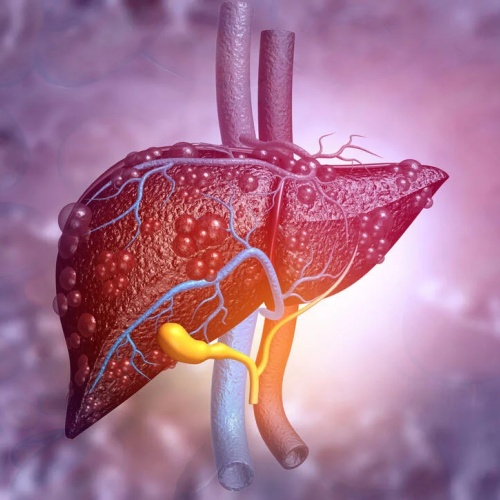

一、疾病背景:脂肪肝已成为全球重要健康问题

近年来,代谢相关疾病显著增加,其中最常见之一是:代谢相关脂肪性肝病(MASH,旧称非酒精性脂肪性肝炎的部分亚型)。该疾病在德国等国家的成年人中患病率约达30%,其特点包括:肝脏脂肪沉积,慢性炎症反应,逐渐进展为肝纤维化甚至肝硬化。

随着疾病进展,患者可能出现:肝功能受损,肝纤维化,甚至肝衰竭或肝癌风险增加。